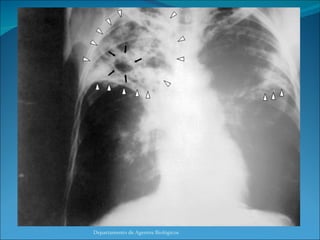

Complejo Primario de Ranke: Neumonitis, Linfangitis y Adenitis Departamento de Agentes Biológicos

Complejo Primario deRanke: Neumonitis, Linfangitis y Adenitis Departamento de Agentes Biológicos